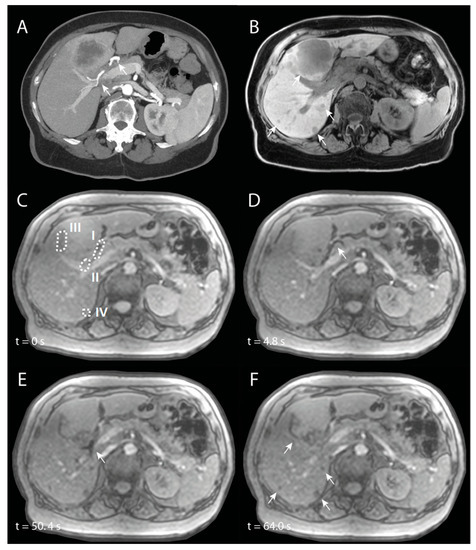

Figure 6 shows an example of near real-time MR images during the injection of 100 mg/mL 165Ho microspheres at a flow speed of 50 mL/min. Directly after the initial injection and saline flush, the bolus of holmium microspheres induces a signal drop in the vessel. In Figure 7, the minimum VOI signal intensity is shown as a function of holmium concentration and pump speed. The maximum relative signal loss observed just distal from the catheter tip was 1%, 3%, 6%, 4% and 12% (range: 9–14%) after injection of, respectively, 10, 25, 50, 75, and 100 mg/mL holmium at a pump speed of 50 mL/min. When pump speed was increased to 100 mL/min, this decreased to 3%, 2%, 4%, 6% and 6%, respectively. The relative signal loss downstream was always lower than directly distal from the catheter tip, with a maximum of 5% (range: 4–5%) at 100 mg/mL holmium and a pump speed of 50 mL/min. A linear correlation between the concentration of microspheres and the extent of signal loss was found in all four scenarios, albeit most clear near the catheter tip (R2 = 0.84 and 0.91) and at a pump speed of 50 mL/min further downstream (R2 = 0.81).

Figure 6.

Intensity measurements over time in the flow phantom, during the injection of 100 mg/mL holmium-165 microspheres with flow set to 50 mL/min. (A) A schematic overview (top) of the images acquired, C = catheter tip, dotted lines indicate 2 VOIs used for signal quantification. Underneath, acquired images are shown at 3 different time points. (B) Subtraction images corresponding to the different time points of A, which more clearly visualize the signal loss induced by the microspheres. (C) illustrates the relative mean intensity per VOI over time. The first drop in intensity (t = 13 s) is a spill of microspheres after loading the catheter, and the second drop in intensity (t = 23 s) is flushing of the catheter with saline.

SIRT was performed in a 74-year-old patient with intrahepatic cholangiocarcinoma. The main lesion was located in Couinaud segments 4A and 4B, and there were multiple satellite lesions in all other liver segments (see Figure 9A,B). A whole-liver SIRT was performed under near real-time MR-imaging, starting with the right hemiliver. The microcatheter was positioned proximal in the right hepatic artery (RHA). In Figure 8, angiography of the entire liver and selective angiography of the RHA are visualized. In Figure 9C–F, different chronological frames of the near real-time imaging during the injection of 30% of the total dose of holmium microspheres are presented. A video of this near real-time imaging series is available online (Supplementary Video S1).

Imaging of a patient with intrahepatic cholangiocarcinoma, of whom the right hemiliver is treated with selective internal radiation therapy. (A) is a maximum-intensity projection of an arterial phase CT in which the right hepatic artery (RHA) is annotated with arrowheads. (B) is a corresponding non-enhanced T1-weighted MRI in which multiple tumours are visible (arrowheads). (C) to (F) are chronologic frames from the near real-time imaged holmium-166 microspheres injection: (C) is just before injection, with VOIs used for signal quantification annotated with dashed lines. In (D), there is loss of signal because of the microspheres in the proximal RHA (arrowhead) and in (E) in the more distal RHA (arrowhead). (F) is the end of near real-time administration, in which there is loss of signal mainly at the tumour sites (arrowheads) that was not visible prior to injection (C).

The aforementioned holmium microspheres were administered in multiple smaller injections (total amount = 126 mg), with catheter flushing with NaCl 0.9% in between, as per usual when using the Customer Kit for microsphere injection. During the first half of the near real-time imaging, a loss of signal is seen in the proximal RHA (Figure 9D). In the second half, this loss of signal was mainly seen more distally in the RHA (Figure 9E), probably as a result of a small breathing motion of the patient, because of which the proximal RHA moved out of plane and the distal RHA entered the imaging plane. Almost immediately after start of injection, loss of signal is seen accumulating in the tumours (Figure 9F).

Quantification of the signal intensities in four different VOIs (proximal RHA (I), distal RHA (II), the edge of the large tumour (III), and the small tumour (IV)) are visualized in Figure 10. The transient loss of signal during the initial injections of the microspheres were clearly visible in the proximal RHA, with the last drop in intensity around 30–40 s, after which the loss of signal occurred more distally in the RHA. In both tumours, there was a rapid decrease in signal intensity during the first injection of microspheres, after which the intensity kept decreasing during the remainder of the injections.